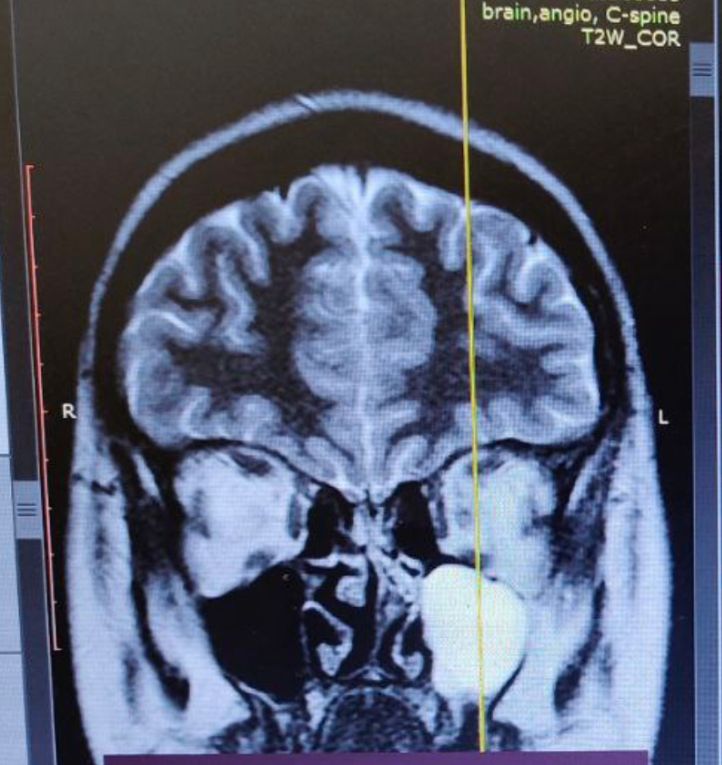

Набор веса ИЦН короткая шейка на 17 неделе